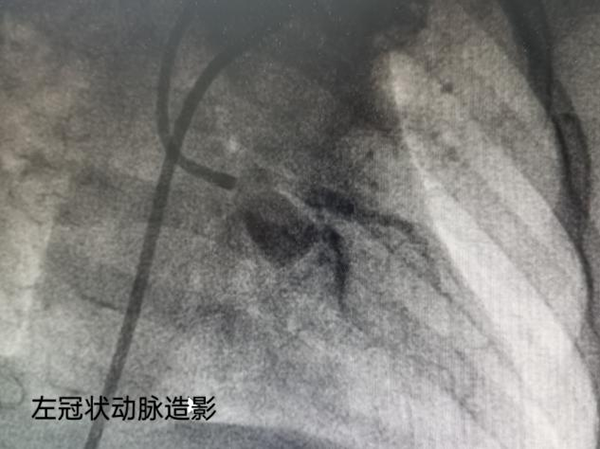

徐醫(yī)附院多學(xué)科合作為7個月大“川崎病”寶寶行冠狀動脈造影手術(shù)

5月23日,患兒完善了術(shù)前檢查,麻醉科進(jìn)行了全面的評估,保證可以進(jìn)行操作后,心內(nèi)科王誠主任醫(yī)師團(tuán)隊采用改良seldinger法穿刺右側(cè)股動脈,為患兒進(jìn)行了單根導(dǎo)管冠狀動脈造影術(shù)。因患兒年齡尚小,術(shù)中導(dǎo)管到位遇到了困難,經(jīng)歷了一個半小時,操作順利結(jié)束,明確了該患兒左側(cè)冠脈近端擴(kuò)張,右側(cè)冠脈近端輕度擴(kuò)張,無冠狀動脈內(nèi)血栓形成。確定了患兒冠狀動脈病變的程度,經(jīng)兒內(nèi)科藥物治療預(yù)計恢復(fù)較好。